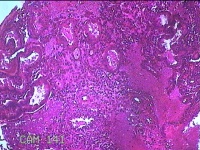

性别

女

年龄

32岁

临床诊断

1.异常子宫出血 2.轻度贫血 3.宫内节育器 4.慢性宫颈炎

一般病史

阴道流血1月余。

标本名称

宫颈内容物

大体所见

灰白暗红色不规则碎组织2.3x1.3x0.3cm一堆。

图2